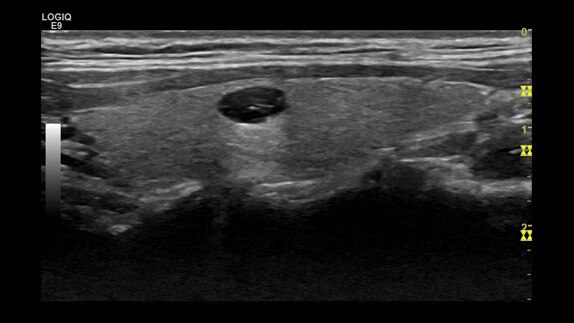

Neurinoma, ML6-15 probu